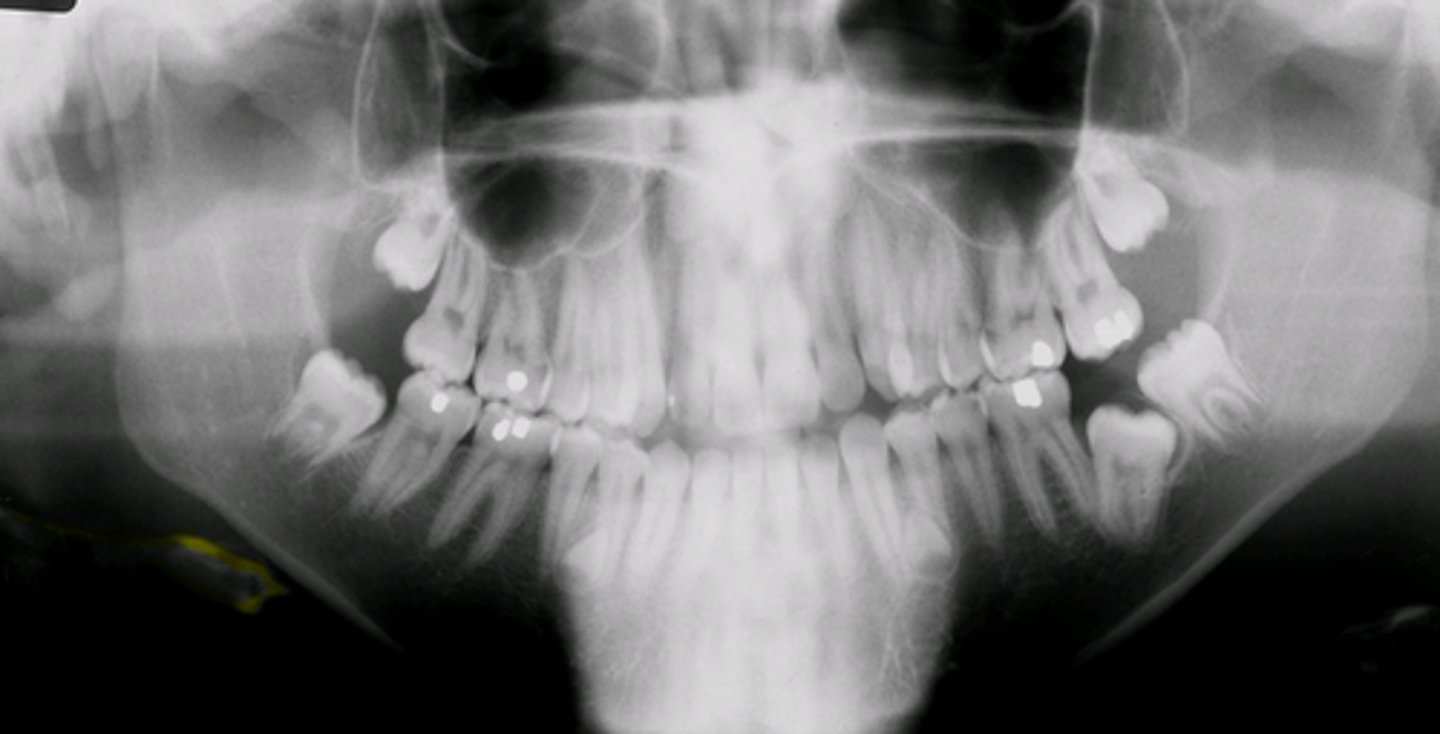

panoramic radiograph

provides full view of the upper & lower jaw

panoramic radiograph purpose

allows us view your head, neck, & jaw, & how they work together as a whole

Impacted third molars are best seen w/what type of radiograph?

Panoramic